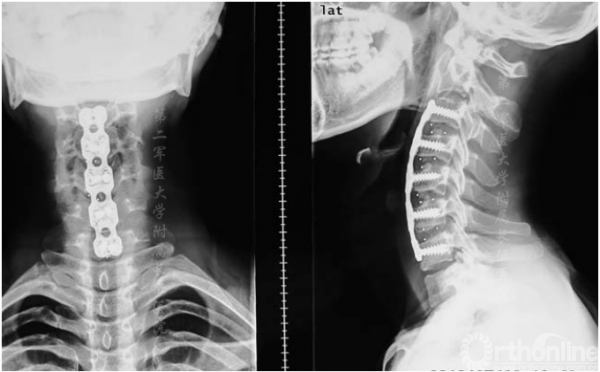

图4.术后6个月x线片显示内固定位置满意,椎体对位齐和骨融合

手术后6个月内,JOA评分从术前平均14分提高到术后平均16.3分。所有患者的JOA恢复率均较为满意。内在肌肉、腕部屈肌和伸肌以及二头肌和三头肌的肌力平均提高了1级。骨移植完全融合(图4),颈椎管容积和颈矢状位满意(图5)。没有发生与手术有关的并发症。